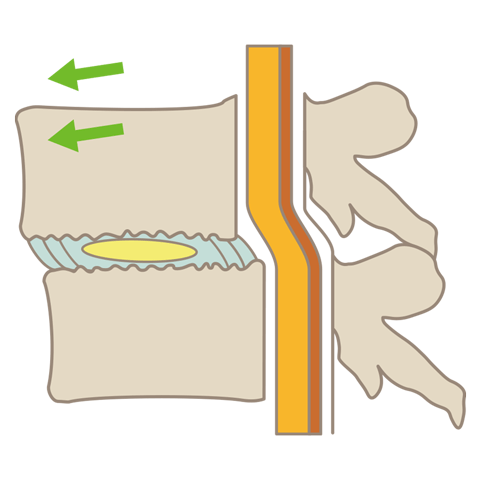

腰椎すべり症

腰椎すべり症とは、背骨が前方や後方にずれてしまう疾患です。腰痛や足の神経障害の他に間欠性跛行(かんけつせいはこう)の症状を引き起こします。